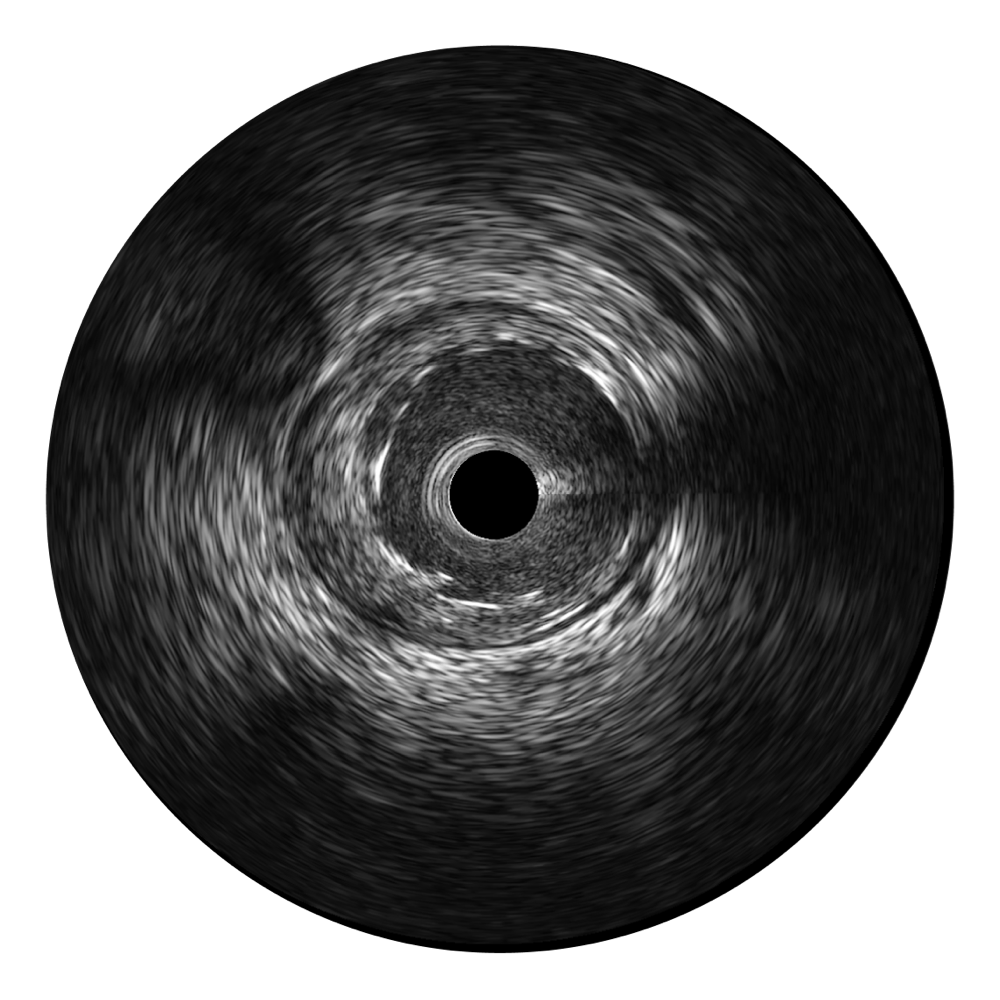

• 新葡的京集团8814检测站宽频IVUS图像

对比传统IVUS导管成像,新葡的京集团8814检测站宽频IVUS图像的近场支架梁显影更细腻,远场中膜外血管仍清晰可辨,兼顾远中近,兼顾分辨力与穿透深度